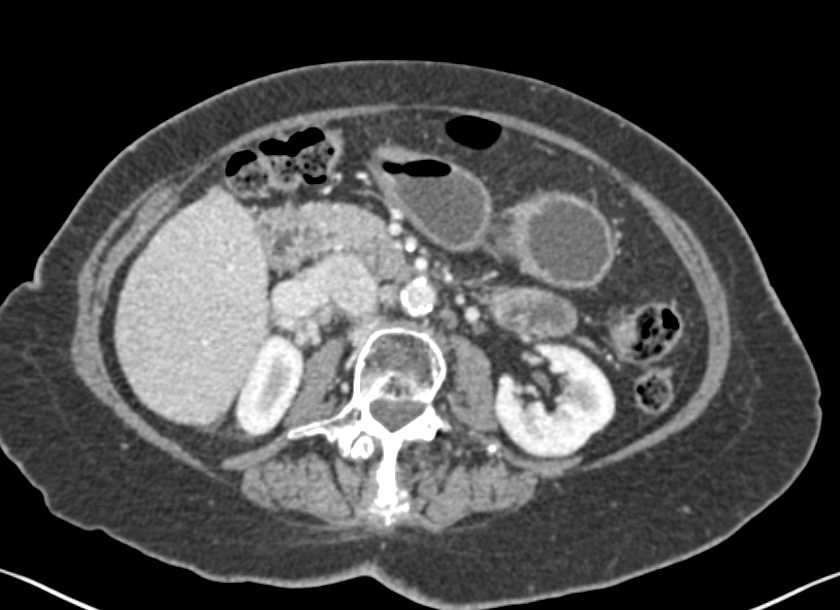

Left Renal Laceration with Hematoma and Contrast Extravasation